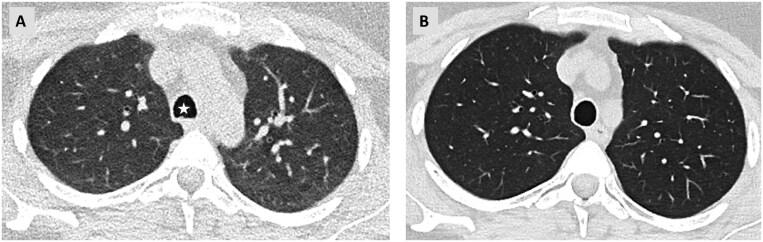

A subset of patients with interstitial lung diseases (ILDs) experiences disease progression despite standard treatment protocols. Similar to idiopathic pulmonary fibrosis, the archetype of progressive fibrotic ILDs, these patients exhibit worsening clinical symptoms, declining lung function, and progressive radiological changes, often resulting in shortened survival. This progressive disease pattern is classified under the term progressive pulmonary fibrosis or progressive fibrosing ILD. Radiological imaging, particularly high-resolution computed tomography (HRCT), is integral to diagnosing ILDs and plays a critical role within multidisciplinary ILD boards. HRCT is instrumental in identifying patients at a higher risk for disease progression and may provide valuable prognostic insights. Additionally, serial imaging is essential for detecting progression over time. While visual assessment remains the primary method for evaluating disease advancement, emerging quantitative techniques, including those utilizing machine learning, are currently undergoing validation.

尽管采用了标准治疗方案,仍有一部分间质性肺疾病(ILD)患者病情进展。与进行性纤维化ILD的原型特发性肺纤维化类似,这些患者表现出临床症状恶化、肺功能下降和影像学改变进展,常导致生存期缩短。这种进行性疾病模式归类为进行性肺纤维化或进行性纤维化ILD。放射影像学,尤其是高分辨率计算机断层扫描(HRCT),对于ILD的诊断不可或缺,在多学科ILD诊疗团队中发挥着关键作用。HRCT有助于识别疾病进展风险较高的患者,并可能提供有价值的预后信息。此外,系列成像对于检测随时间的进展至关重要。虽然视觉评估仍然是评估疾病进展的主要方法,但包括利用机器学习的技术在内的新兴定量技术目前正在进行验证。